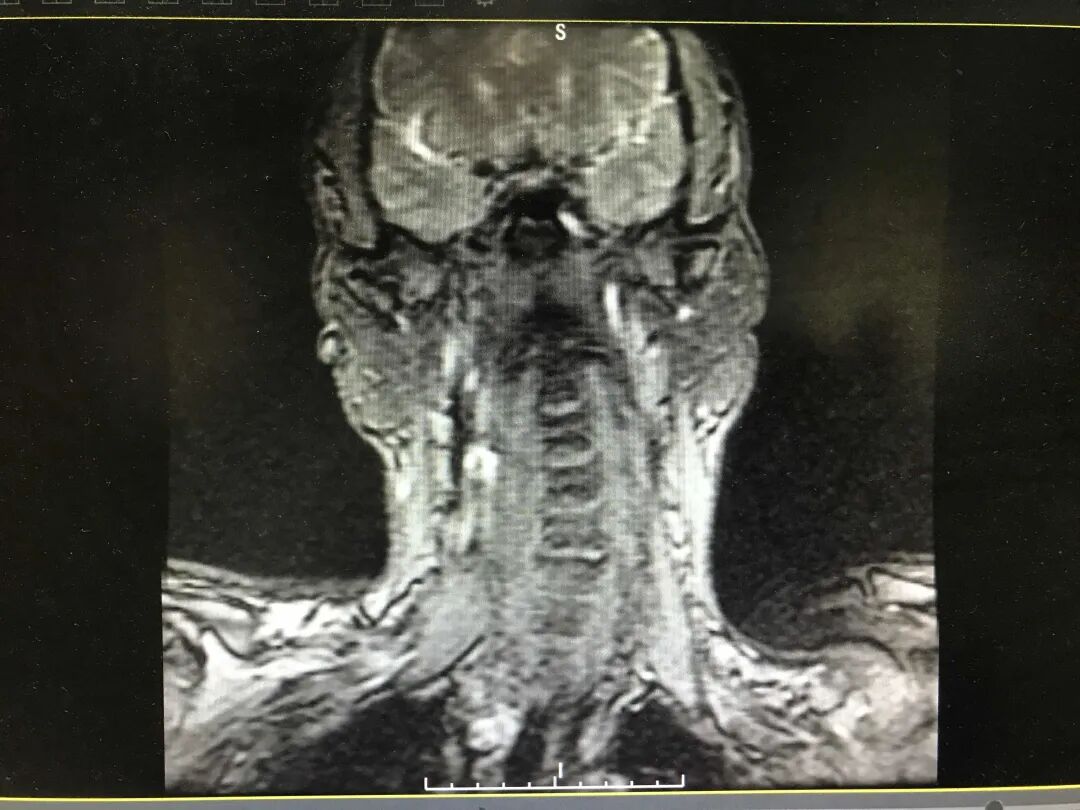

最近,48岁的邓大哥已经连续几天没睡一个好觉了,其颈部及左上肢疼痛明显,无法仰卧也不能俯卧,只能勉强右侧卧位,严重影响睡眠和正常生活。

张燕伟主任结合相关检查,辨证诊疗,采取针刺、推拿、拔罐等治疗方法以疏经通络止痛。